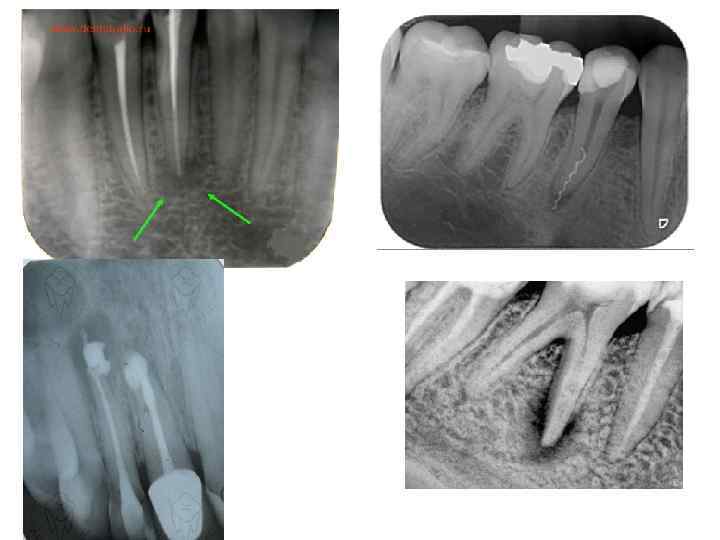

Диагностика хронического периодонтита • основывается на клинической картине и рентгенологических данных. На рентгенограмме при гранулирующем периодонтите обнаруживаются типичные изменения — очаг разрежения костной ткани в области верхушки корня. Линия периодонта в этом отделе не видна из -за инфильтрирующего роста грануляционной ткани, приводящего к рассасыванию стенок лунки, а также цемента и дентина корня. Поверхности их становятся неровными. Эту неровность выявляют более отчетливо со стороны костной ткани, в которую из периодонта идут небольшие выросты

Диагностика • основывается на клинической картине, но чаще всего на рентгенологических данных. На рентгенограмме при гранулематозном периодонтите в околоверхушечной области виден округлый очаг разрежения костной ткани с четкими ровными границами. При правильно проведенном консервативном лечении на месте гранулематозного очага выявляют изменения, характерные для фиброзного периодонтита, или образование участка склерозированной костной ткани

Диагностика • основывается на данных рентгенографии. На рентгенограмме выявляют расширение линии периодонта, главным образом у верхушки корня зуба. Иногда в результате гиперцементоза обнаруживают значительное утолщение верхушечного участка корня. Костная пластинка, ограничивающая расширенную линию периодонта, нередко утолщена, склерозирована

Схематическая картинка рентгенограмм хронических периодонтитов